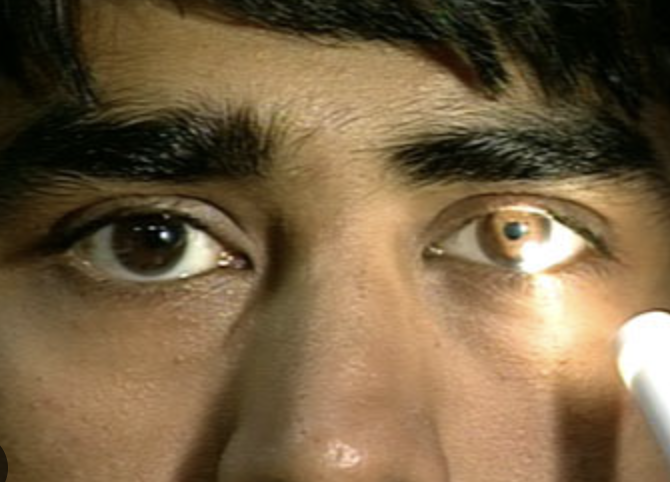

Inspect iris and pupil

Eleventh Step of Eye Assessment

Inpect shape and color of iris and size and shape of pupil

If pupil is larger, smaller, or different sizes, measure pupils against a gauge

How to conduct 11. Inspect iris and pupil?

Iris is round, flat, and evenly colored

Pupil is round with a regular border, and is centered in the iris

Pupils are normally equal in size (3-5 mm)

Normal finding for 11. Inspect iris and pupil

Inequality in pupil size less than 0.5 mm

Normal variation for 11. Inspect iris and pupil

Irregularly shaped irises

Miosis

Mydriasis

Anisocoria

4 Abnormal Findings for 11. Inspect iris and pupil

Miosis

4 Abnormal Findings for 11. Inspect iris and pupil

Aka pinpoint pupils

Characterized by constricted and fixed pupils

Possibly a result of narcotic drugs or brain damage

Anisocoria

4 Abnormal Findings for 11. Inspect iris and pupil

Pupils of unequal size

If greater in bright light compared with dim light, the caused may be trauma, tonic pupil (caused by impaired parasympathetic nerve supply to iris), and oculomotor nerve paralysis

If greater in dim light compared with bright light, the cause may be Horner’s syndrome (caused by paralysis of the cervical sympathetic nerves and characterized by ptosis, sunken eyeball, flushing of the affected side off the face, and narrowing of the palpebral fissure)

Mydriasis

4 Abnormal Findings for 11. Inspect iris and pupil

Dilated and fixed pupils, typically resulting from CNS injury, circulatory collapse, or deep anesthesia

Pupillary reaction to light

Twelfth Step of Eye Assessment

Darken the room and ask client to focus on a distant object

Shine a light obliquely into one eye and observe the pupillary reaction

How to test 12. Pupillary reaction to light?